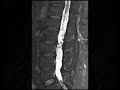

Spinal Hemangioblastomatosis

These images demonstrate on first glance innumerable tiny flow voids surrounding the cauda equina which may lead one to consider a dural arteriovenous fistula. Post contrast images show that there are innumerable avidly enhancing masses which were predominantly isointense to CSF on noncontrast images. The differential includes drop metastases, schwannomatosis, or hemangioblastomas in a patient with Von Hippel Lindau (VHL). This patient had known VHL which clinches the diagnosis of spinal hemangioblastomatosis.